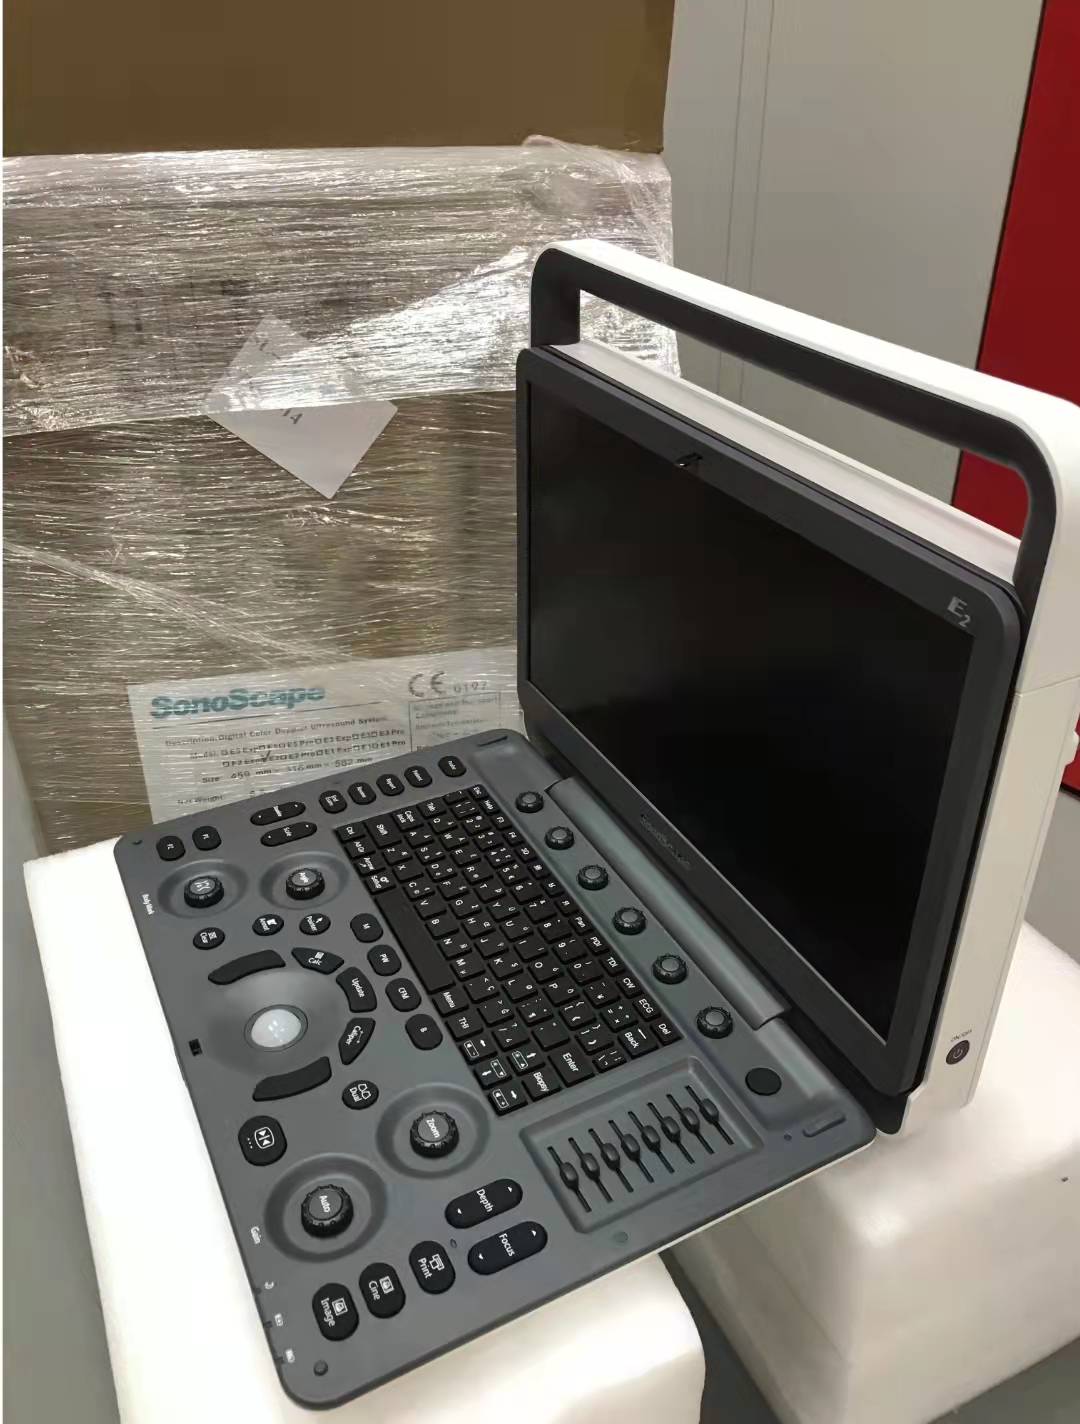

E2 Pro was born out of a desire to better meet consumers' demands for quality and value for money. Unlike sonoscape E2, it is streamlined and even easier to operate than any other entry-level system,the E2 PRO is packed with complete standard ultrasound functions and a full library probes for different applications.

Specification

| Model Number | SonoscapeE2 |

| Size | 378mm×352mm×114mm (W×H×D) |

| Weight | Approx. 6.5kg (at most, including battery) |

| Approx | 6.1kg (at most, without battery) |

| Monitor | 15.6“widescreen and high-resolution color LCD monitor, LED backlight, anti-flickering and vertically and horizontally rotatable |

| Probe port | one (two ports can be equipped by order) |

| Frame Rate | Up to 80fps(Probe Dependent) |

| options | CW/CMM/TDI/AMM B Mode Prospective Saving SR flow Vis-Needle 2D Panoramic Imaging LGC: Lateral gain compensation Wifi and ECG Module |

| Accessories | Trolley Backpack Large Capacity Battery Color ink-jet printer: HP Officejet Pro 8000/HP Office jet Pro K5400 B/W video printer: SONY UP-D897/SONY UP-X898MD Footswitch External DVD and buletooth Controller |